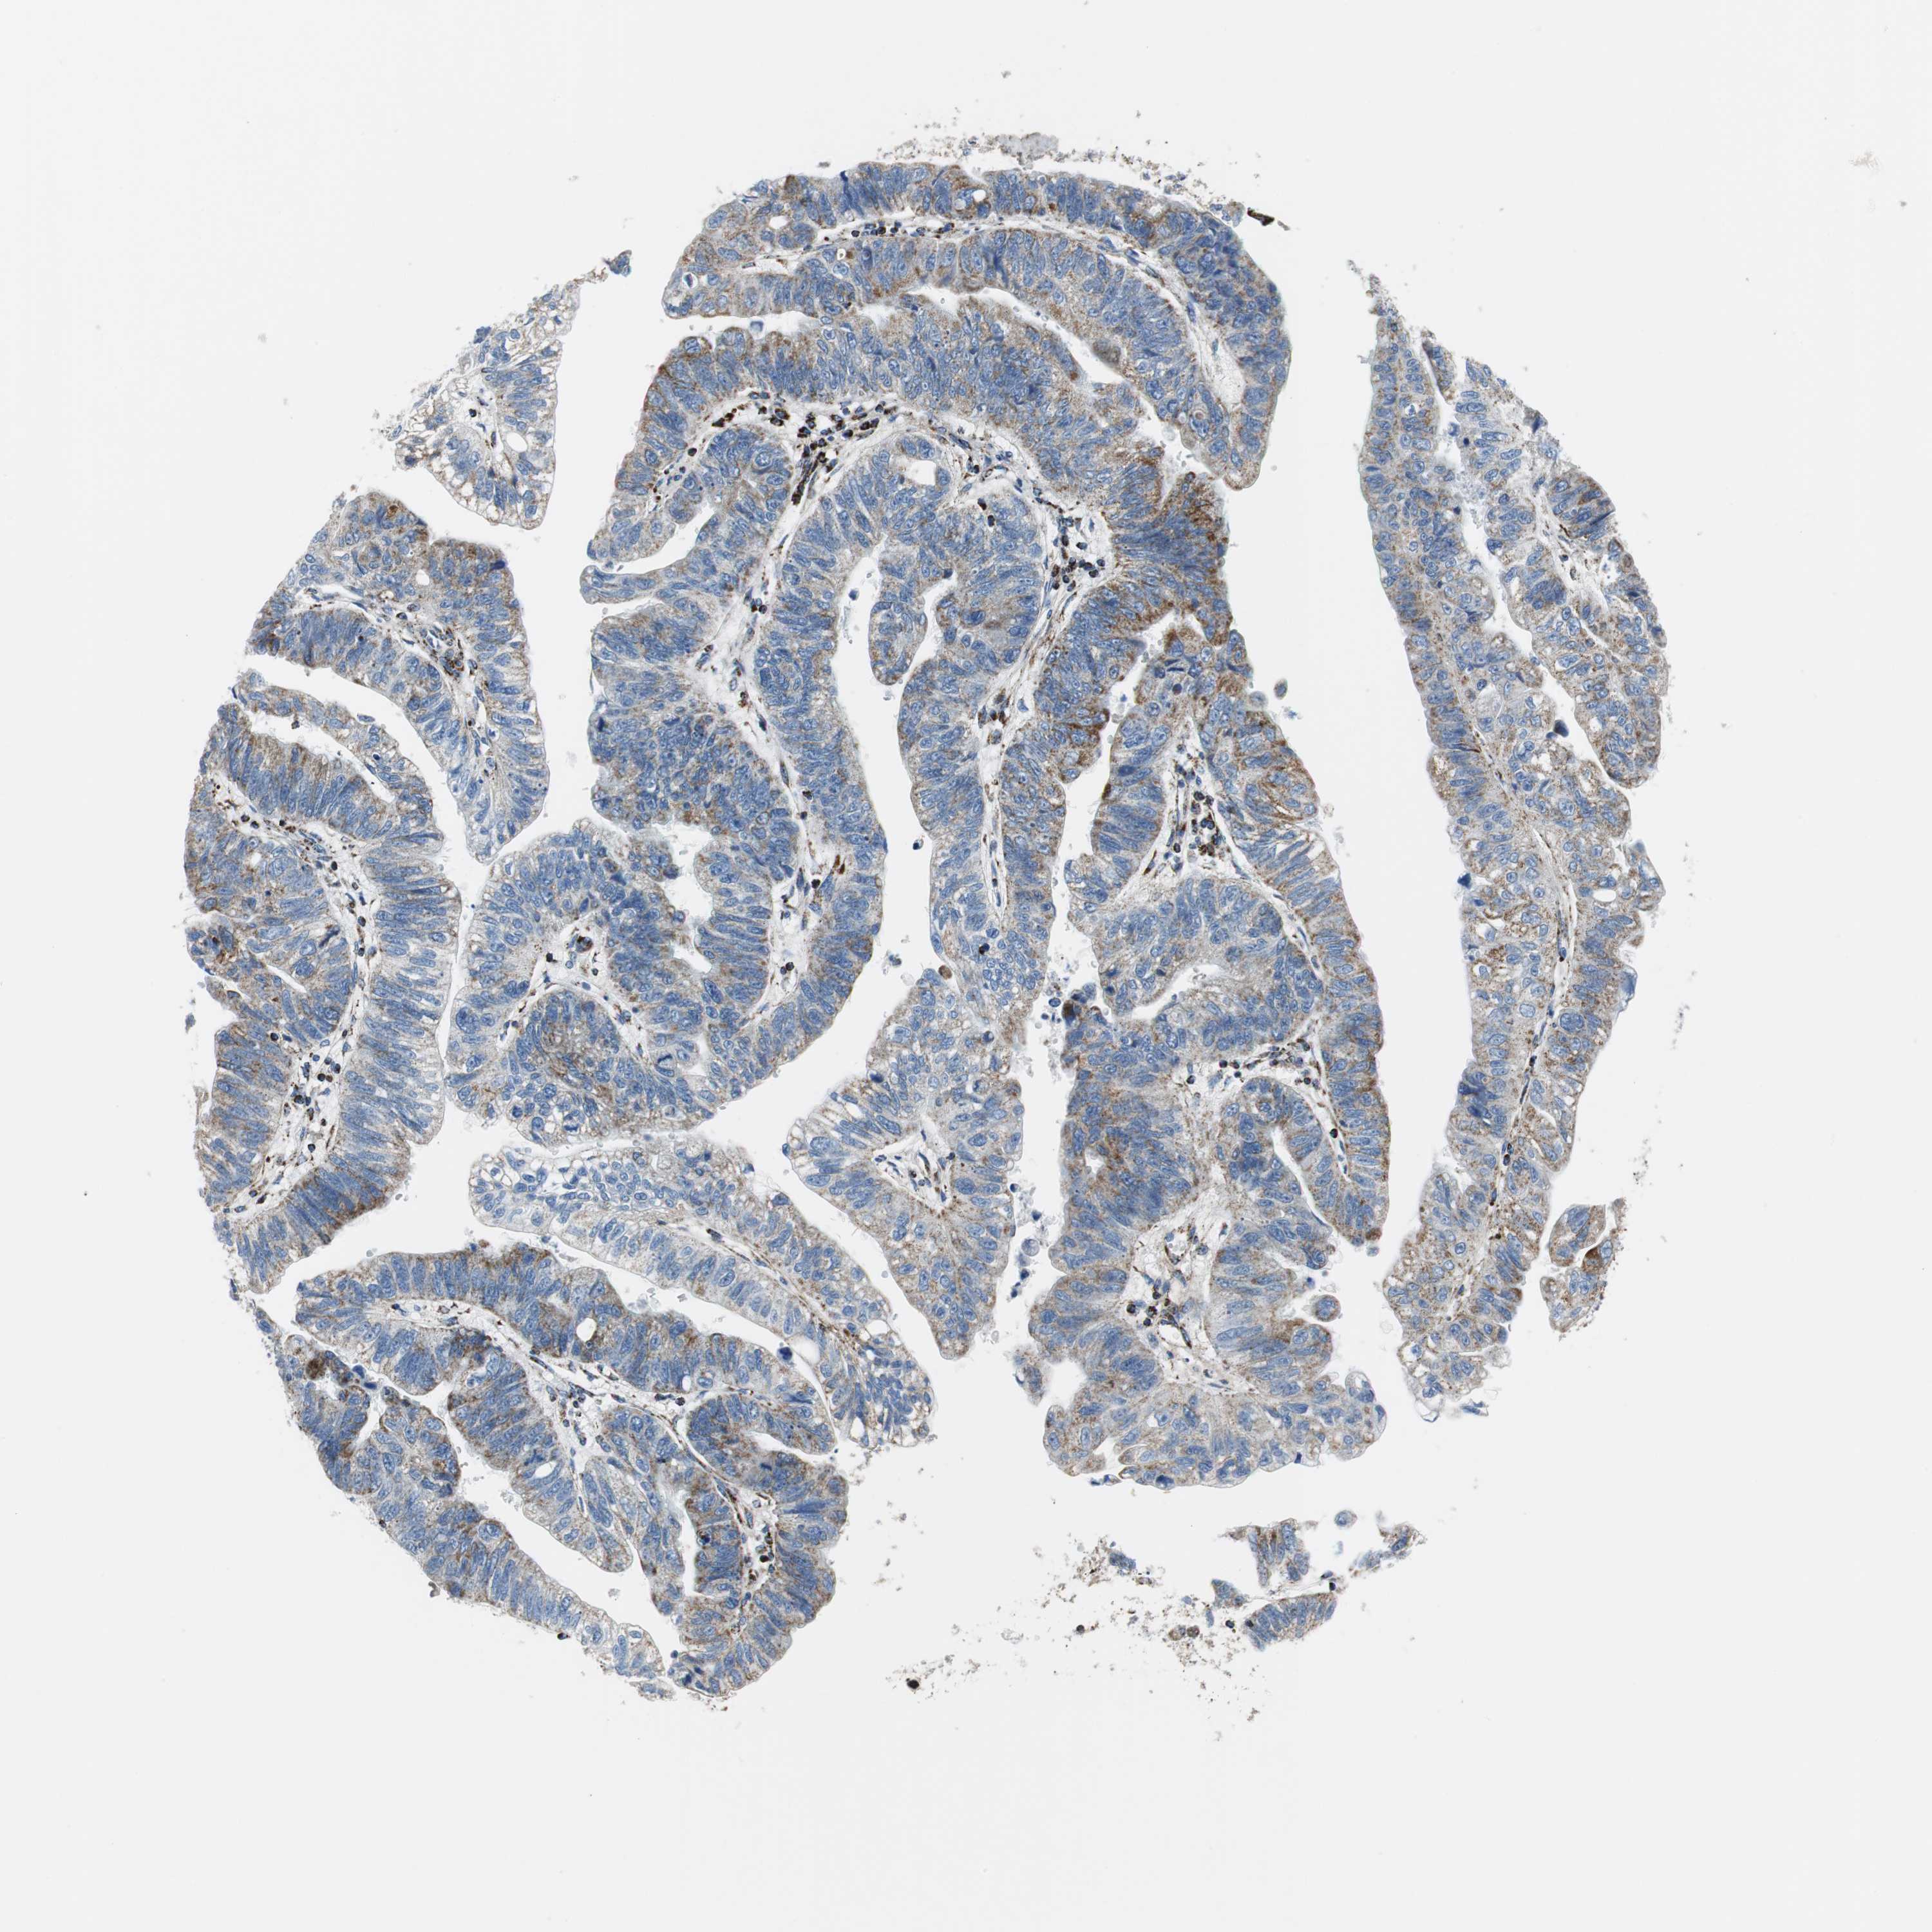

STOMACH CANCER - Protein expressioni

A mouse-over function shows sample information and annotation data. Click on an image to view it in a full screen mode. Samples can be filtered based on level of antibody staining by selecting one or several of the following categories: high, medium, low and not detected. The assay and annotation is described here.

Note that samples used for immunohistochemistry by the Human Protein Atlas do not correspond to samples in the TCGA dataset.

Antibody stainingi

Antibody staining in the annotated cell types in the current human tissue is reported as not detected, low, medium, or high, based on conventional immunohistochemistry profiling in selected tissues. This score is based on the combination of the staining intensity and fraction of stained cells.

Each image is clickable and will lead to virtual microscopy that enables deeper exploration of all samples and also displays staining intensity scores, fraction scores and subcellular localization as well as patient and tissue information for each sample.

Antibody CAB007055

Staining

High

Medium

Low

Not detected

Intensity

Strong

Moderate

Weak

Negative

Quantity

>75%

75%-25%

<25%

None

Location

Nuclear

Cytoplasmic/membranous

Cytoplasmic/membranous,nuclear

Adenocarcinoma, NOS

Adenocarcinoma, High grade